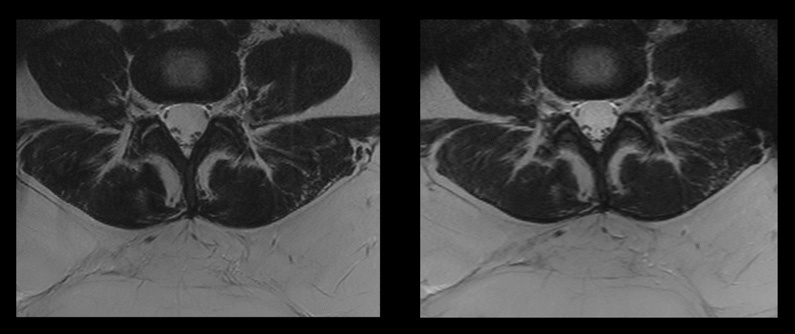

Comparison of two spine sequences with and without Compressed SENSE

Comparison of two spine sequences with and without Compressed SENSE.

Image on the left: Conventional scan with SAR level of 2.5W/kg and a scan time of 7:33 min.

Image on the right: Compressed SENSE scan with SAR level of 1.9W/kg and a scan time of 3:21 min.